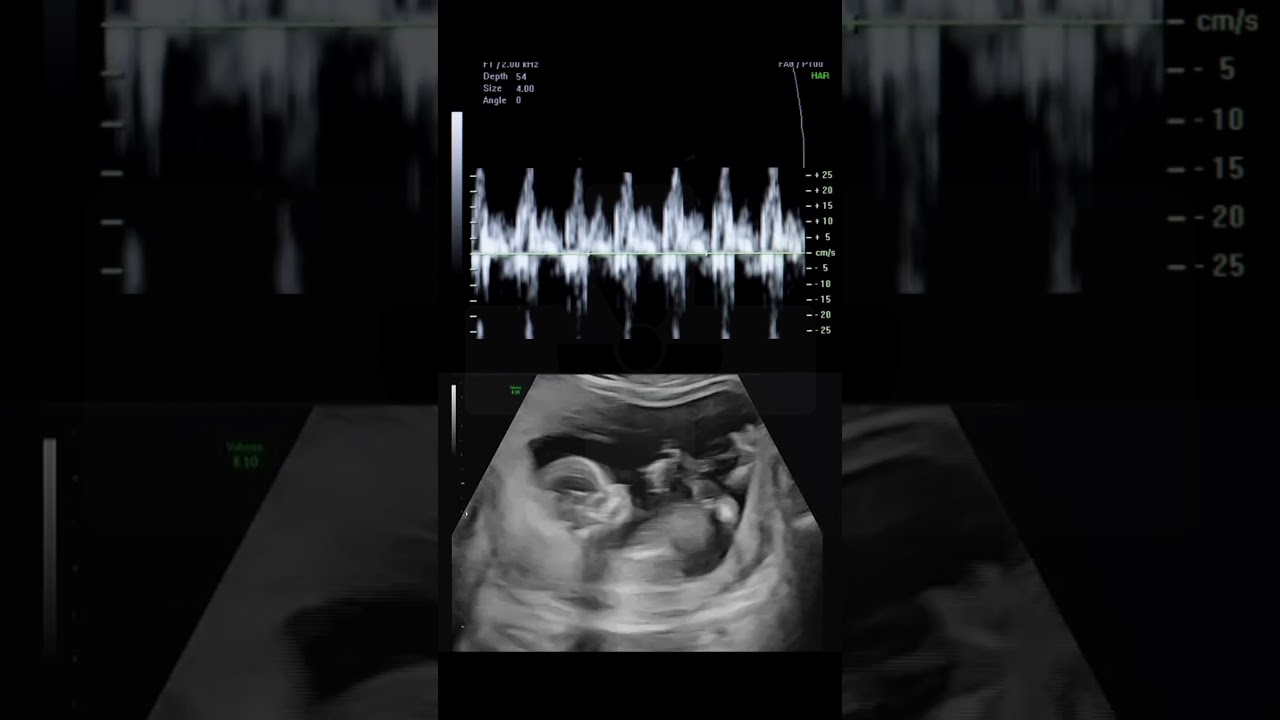

Fetal Heart With Doppler Heartbeat Waveform Showing A Normal Cardiac

Fetal Doppler Ultrasound Pregnancy In Bd Baby S Heartbeat Movement In pregnancy, this allows doctors to assess blood flow patterns in the umbilical cord, placenta, and fetal organs without any harm to mother or baby. the examination produces visual waveforms that represent blood flow throughout the cardiac cycle. Doppler fetal heartbeat detectors are moderately directional, so unless you happen to aim it directly at the fetal heart initially, you will need to move it or angle it to find the heartbeat. confirm a normal rate, and listen for any abnormalities in the rhythm of the fetal heart beat.

Fetal Doppler Ultrasound Pregnancy In Bd Baby S Heartbeat Movement Fetal doppler assessment plays a crucial role in monitoring the fetal well being during pregnancy. this non invasive technique assesses blood flow dynamics in key fetal vessels, namely the umbilical artery, middle cerebral artery, and ductus venosus. Baby heart doppler devices rely on doppler ultrasound technology, which uses high frequency sound waves to detect movement and blood flow. in pregnancy, they are commonly used to identify and monitor the baby’s heartbeat. Effective fetal cardiac screening should maximize detection of structural anomalies and (according to available expertise and resources) abnormalities of function and rhythm, as part of routine prenatal care. The fetal doppler is a handheld device that detects and amplifies the sound of a baby’s heartbeat during pregnancy. it’s ultrasound quality & budget friendly in bd.